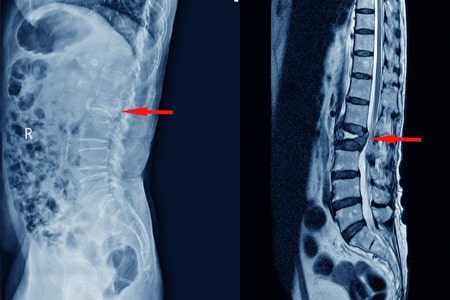

Los AINE y la teriparatida pueden ser las opciones de tratamiento preferidas para el tratamiento del dolor agudo en las fracturas vertebrales por compresión osteoporóticas. Aunque la calcitonina también demostró ser beneficiosa, su perfil de seguridad y los posibles efectos adversos restringen su aplicación generalizada. La evidencia limitada sobre los aparatos ortopédicos y los analgésicos subraya la necesidad urgente de investigaciones futuras. JAMA Netw Open. 3 de septiembre de 2024